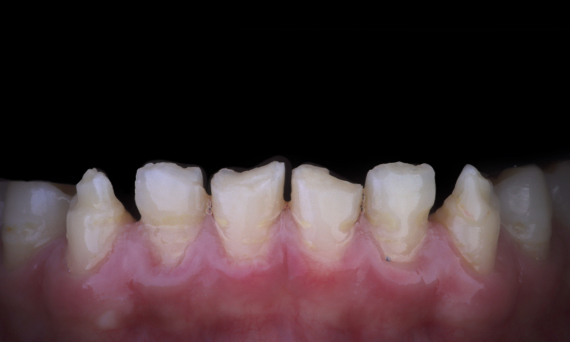

Avant : Situation clinique préopératoire. Traumatisme des incisives centrales maxillaires

Après : Restaurations collées.